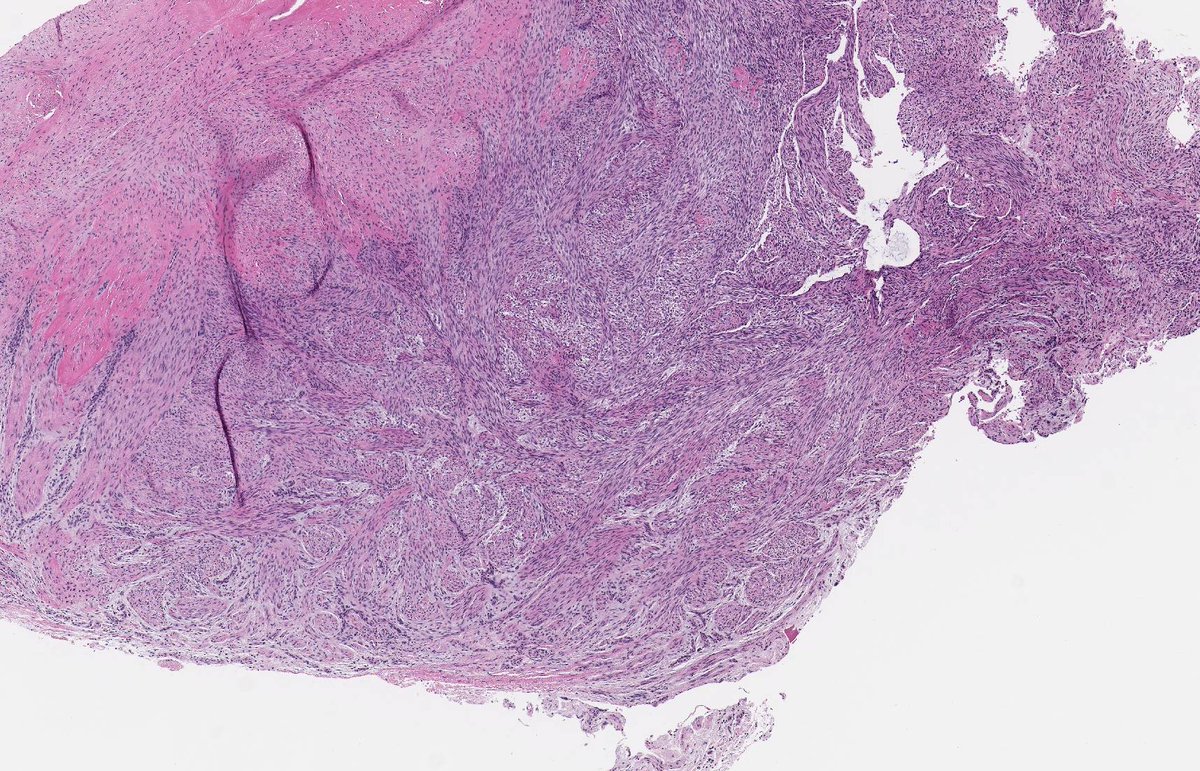

MALIGNANT PERIPHERAL NERVE SHEATH TUMOUR. Underlying NF1. IHC: SOX10, H3k27me3. NB: spindle-epithelioid cells with pale amphophilic cytoplasm; ovoid-round nuclei with moderate pleomorphism and conspicuous mitotic activity; variable collagenous-myxoid stroma.

1

21

60